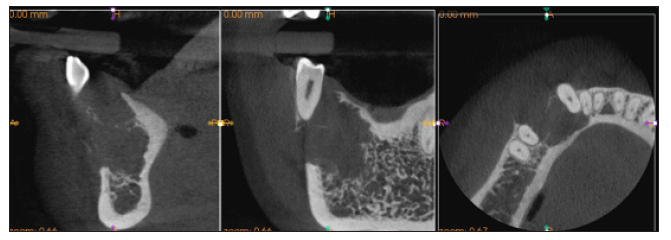

Se ordenó tomografía computarizada haz cónico (TCBC) sectorizada, la cual mostró un amplio campo de la lesión multilocular de limites definidos, trabeculado; la cortical vestibular se evidenció totalmente reabsorbida, sin perforación de la cortical lingual, la cual también se evidenció parcialmente reabsorbida. No se observó afectación de la basal mandibular ni reabsorción de los órganos dentales implicados (figura 2).